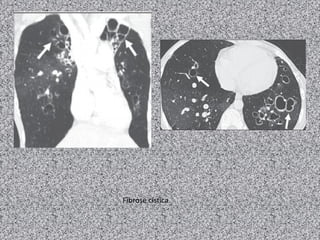

Fibrose cística

Fibrose cística: imagem

TACR de tórax:

Bronquiectasias (principal achado):

Pode ser dos 3 tipos; geralmente bilaterais;

Predomina nos lobos superiores;

Espessamento brônquico;

Impactação mucoide pode ocorrer;

Nódulos centrolobulares;

Árvore em brotamento;

Consolidações;

Lesões císticas ou bolhosas nos ápices;

Linfonodomegalias hilar e mediastinal

Anormalidades pleurais (derrame e/ou espessamento)

Homem de 37 anos com tosse crônica e dispneia progressiva